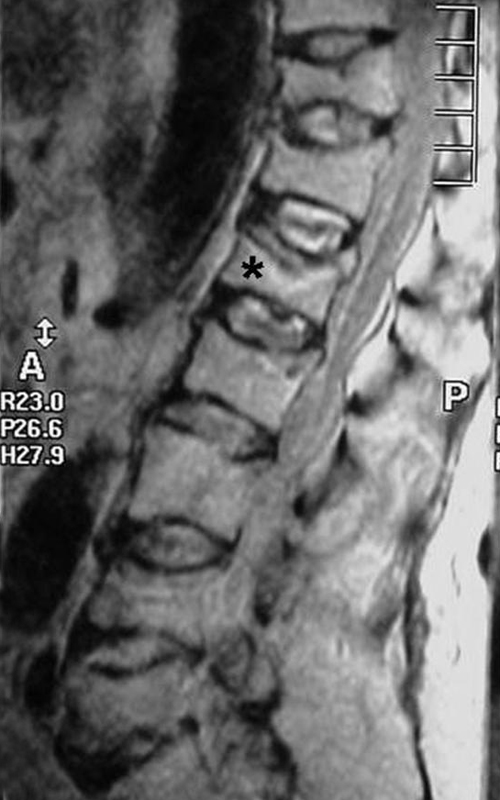

A free medical education seminar series for everyoneA FREE spine education seminar series for everyone Back pain has many faces and to many people it can be distressing, disabling or even frightening. Whether back pain comes from a strain, degenerative disc disease, a herniated disc, spinal stenosis, spondylolisthesis, a complex deformity or even a fracture, there are many options that can help you to live an active lifestyle. Additionally, osteoporosis is another disease that you may not even know you have. Learn from these dynamic experts about the various types of back problems and the latest treatments available. We will discuss the problems, the solutions and leave time for your questions to help you be active. Talk with the experts and get your concerns addressed. Spine Program